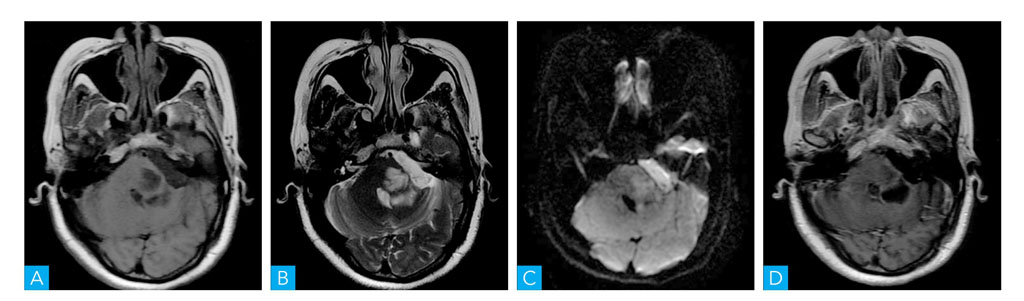

图1-1-2 头部MRI扫描

A.轴位T1WI;B.轴位T2WI;C.轴位T2-FLAIR;D.轴位T1WI增强;E.冠状位T1WI增强;F.矢状位T1WI增强

病人为青年女性,慢性起病,临床表现为头晕、复视、左耳听力下降、面部发麻。CT表现为左侧桥小脑角区域稍低密度占位病变,病灶内未见钙化及出血改变,增强扫描呈环形强化,邻近内听道未见增宽,颅底骨质未见增生或破坏改变。MRI表现为左侧桥小脑角区域肿物,边缘呈等T1、稍长T2信号,中央区可见液化坏死,增强扫描呈明显环形强化,与脑组织分界不清,邻近脑干及左侧小脑可见大片水肿信号影,左侧面听神经未见增粗及强化,左侧内听道未见增宽、四脑室稍受压变窄。根据以上特点,该病变定位于脑内,考虑为弥漫性星形细胞瘤。

本病例为青年女性,慢性起病,病灶位于左侧桥小脑角区,CT表现为稍低密度肿块,病灶内见更低密度区,病灶内未见钙化及出血改变,增强扫描呈环形强化,邻近内听道未见增宽,颅底骨质未见增生或破坏改变;MRI上表现为左侧桥小脑角区肿物,病灶内可见液化改变,边缘呈等T1稍长T2信号,病灶与脑组织分界不清,增强扫描呈明显环形强化,邻近脑干及左侧小脑可见大片水肿信号影,左侧面听神经未见增粗及强化,左侧内听道未见增宽、第四脑室稍受压变窄。根据以上特点,考虑为弥漫性星形细胞瘤。该病发生在桥小脑角区域,需要与听神经瘤、脑膜瘤、表皮样囊肿相鉴别。仔细观察肿瘤密度或信号特点,与周围脑膜关系,邻近听神经及内听道是否改变,颅骨骨质有无异常等情况则不难鉴别。